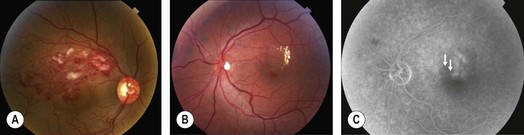

Patients may complain of visual blurring, distortion or metamorphopsia. On examination, intraretinal flame and blot shaped hemorrhages as seen in the territory of a dilated, tortuous retinal vein are present (Fig. 14.1.1). Given the distribution of retinal veins the accompanying pathology of BRVO almost never crosses the horizontal raphe. Cotton wool spots, retinal edema in the area drained by the occluded branch, collateral vessels and occasionally retinal neovascularization and vitreous hemorrhage may be seen. Vision loss is largely due to of retinal edema and may sometimes be secondary to retinal ischemia.

Fluorescein angiography is of value when the hemorrhages start clearing to assess perfusion. It may also be employed earlier to check for retinal neovascularization.